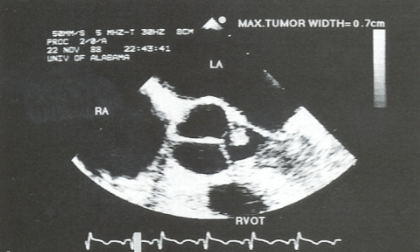

Myxoma

neoplasm that arises from endocardial tissue

80% located in LA

RA 2nd most common

usually attached by a stalk to the IAS

“pedunculated”

often arises from IAS

near region of fossa ovalis

Myxoma 2D findings:

visualization of myxoma

allows detection, location, + sizing

exaggerated motion of myxoma

d/t prolapsing from LA into the LV